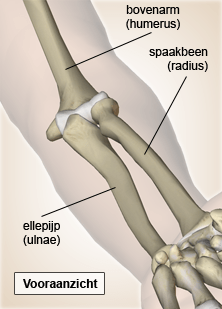

Elleboog